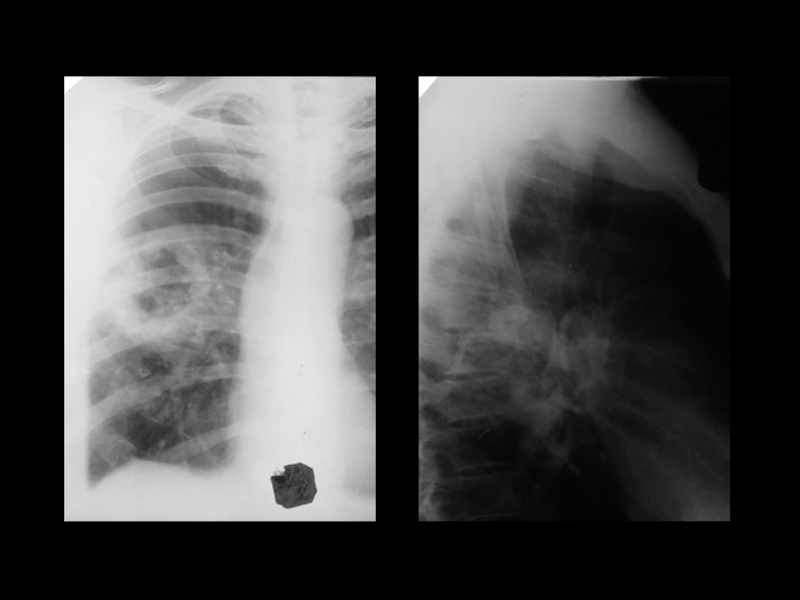

Центральный рак легкого

ЛУЧЕВАЯ ДИАГНОСТИКА РАКА ЛЕГКОГО

АКТУАЛЬНЫЕ ВОПРОСЫ РЕНТГЕНОЛОГИИЦентральный рак легкогоЛУЧЕВАЯ ДИАГНОСТИКА РАКА ЛЕГКОГО